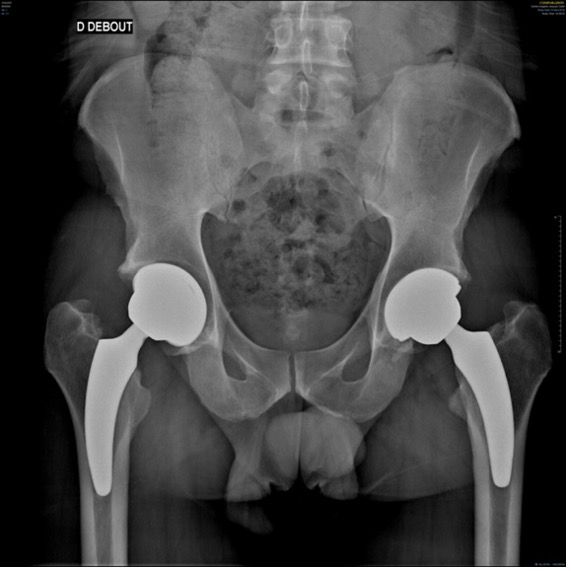

Hips in coxa vara sometimes present a very significant femoral offset which may be prove to be difficult to restore using standard stems. In this case, a varus-tilted or lateralized stem should be used and this will require a very low femoral cut, often with loss of residual femoral offset and a risk of lengthening the lower limb. Positioning a straight cementless stem in varus runs the risk of trajectory error and femoral pain. If a modular neck implant is chosen, the increased lever arm results in significant pressures on the modular neck and neck-head junction with risks that are already known. Finally, even with a cemented stem, positioning it in varus will increase the pressures on the bone-cement interface, with a risk of early loosening. With calcar-guided short stems, the stem will follow the medial cortex of the neck (which will have been cut high), naturally finding a varus tilt and making it possible to reproduce even very significant offsets (Figs 4 and 5).

In total hip replacement, there is often a relative reduction in the acetabular offset due to burring off a few millimetres, which is necessary for the implant to fit in the hip socket cavity, and this is compensated for by a relative increase in femoral offset, to restore the overall hip offset.